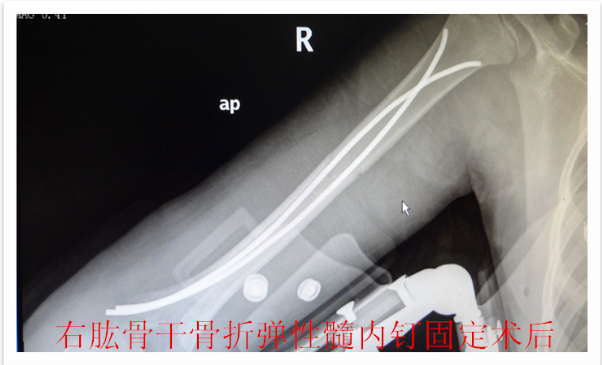

儿童骨折的微创治疗--四肢骨折的弹性髓内钉技术(骨科)

儿童四肢骨折较为常见,保守治疗仍是儿童骨折的重要 治疗方法之一,如牵引,单纯石膏固定等。 往往用时较长,患儿的舒适程度不够,影响患儿及时返回学校学习,这些因素越来越多地影响儿童骨折治疗方法 的选择 。儿童骨折手术治疗的比例较前增加,而传统的手术治疗创伤大,恢复慢,并发症多,如钢板,那是针对成人骨折研发的,用一个坚硬的内固定物固定一个有弹性的骨组织是一个矛盾 ,弹性髓内钉内固定解决了这个矛盾。有人说,弹性髓内钉的出现是上天对儿童的恩惠。的确,弹性髓内钉是治疗小儿长管状骨骨骨折的一种理想、可靠的内固定方法。弹性髓内钉技术发源于法国,在欧洲广泛应用后,现已为全球所接受,被称为是儿童骨科界的一次革命。徐州儿童医院骨一科应用弹性髓内钉技术治疗四肢长管状骨骨折,具有创伤小、恢复快、并发症相对少,孩子能较快恢复正常生活、学习等优点。该技术先将骨折闭合复位,通过微小的切口将特制的弹性髓内钉置入骨髓腔,达到固定骨折的目的。适用于肱骨,股骨,尺桡骨等部位的常见骨折(图)。